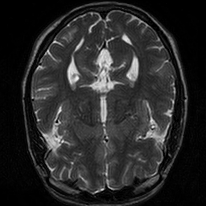

4.4 Qualitative Evaluation

In Figure 5 we analyze the prediction quality of our and compared approaches in a qualitative way. Considering modality propagation in MRI, we see that usage of uncertainty-aware patch invariance (UAPI) gives a better detailed weighting of the cerebrospinal fluid in the middle of the brain. In general, employing patch invariance yields better preservation of fine structures. This observation also applies to accelerated MRI enhancement. In particular, CUT and UAPI provide comparatively sharper knee images with more high-frequency details than the other methods.